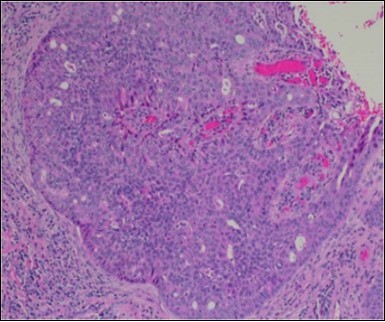

Granular arrangement of malignant cells and intercellular bridges are conspicuous with the demonstration of nuclear atypia, pleomorphism, prominent mitosis and tumour necrosis. A peripheral palisade is discernible within the cellular aggregates. Mitotic figures are common and can be quantified as up to 12 mitosis/ high power field. Tumour differentiation can prominently be of the ductal category with the demonstration of intra-cytoplasmic lumina. Comedo type tumour necrosis is evident along with foci of squamous differentiation The neoplasm is reactive to periodic acid Schiff ‘s (PAS) stain. (Figure 1, Figure 2, Figure 3, Figure 4, Figure 5, Figure 6, Figure 7, Figure 8, Figure 9, Figure 10, Figure 11, Figure 12, Figure 13.

Figure 3.Cohesive accumulations with numerous ductular articulations of carcinoma cells in eccrine porocarcinoma (15).

Figure 4.Cellular atypia, mitosis and focal necrosis in eccrine porocarcinoma(16).

Figure 5.Sweat glandular articulations and malignant cellular aggregates with cystic spaces in eccrine porocarcinoma(17).

Figure 6.Epidermal continuity with aggregates of atypical, solid and cystic epithelial cell nests in eccrine porocarcinoma (18).

Figure 7.Aberrant and malignant epithelium with cellular proliferation and pleomorphism in eccrine porocarcinoma with frequent mitosis(19).